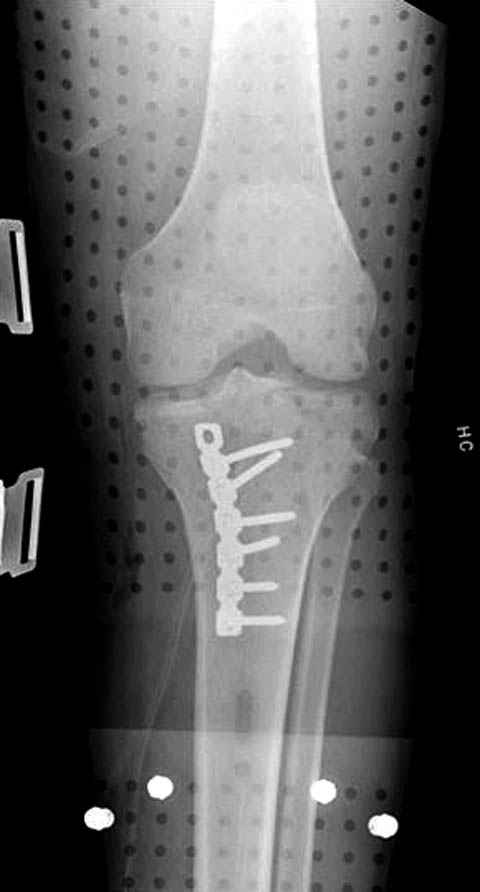

Уважаемые коллеги! В прошлую пятницу больной прооперирован - как и планировалось мыщелковая LCP от ChM. Малоинвазивно не получилось - один большой доступ :(. (но с минимальным скелетированием б/б кости). Наружный мыщелок собрали, но по контролю видно, что задне-медиальный отдел метаэпифиза смещен. Фиксировать не стали (?). 4-е сутки после операции - по м/тканям без проблем. Дополнительная иммобилизация синтетическим тутором.

P. S. перелом диафиза на контроле не совсем захвачен, но проблем там нет. Приношу извинения за низкое качество Р-грамм - выполнены на сканере (фотоаппарат не работает :)) .

Трудно поверить, что разрекламированная Ортопедическая школа Восточной Украины позволяет такие странные снимки? На прямом снимке сохранен общий контур плато, но не известна судьба импрессии суставной поверхности. На полубоковой?, оставлен без репозиции задне-медиальный отдел, и навряд ли после такой фиксации можно удовлетвориться результатом.

Такая ситуация характерна для многих, когда принимается ошибочное решение, т.е пытаются фиксировать одним имплантом переломы двух мыщелков. Латеральная пластина приемлема только для тех случаев, когда сохраняется интактным медиальный диафизарный кортекс и отсутствует фрагментация на верхушке медиального перелома.

Здесь как раз тот случай, когда результат зависит не только от мастерства хирурга, но и от наличия современных методов исследования. Например, КТ которая поможет рассчитать направления шурупов и установку импланта. Кроме этого, поможет определиться с доступом.